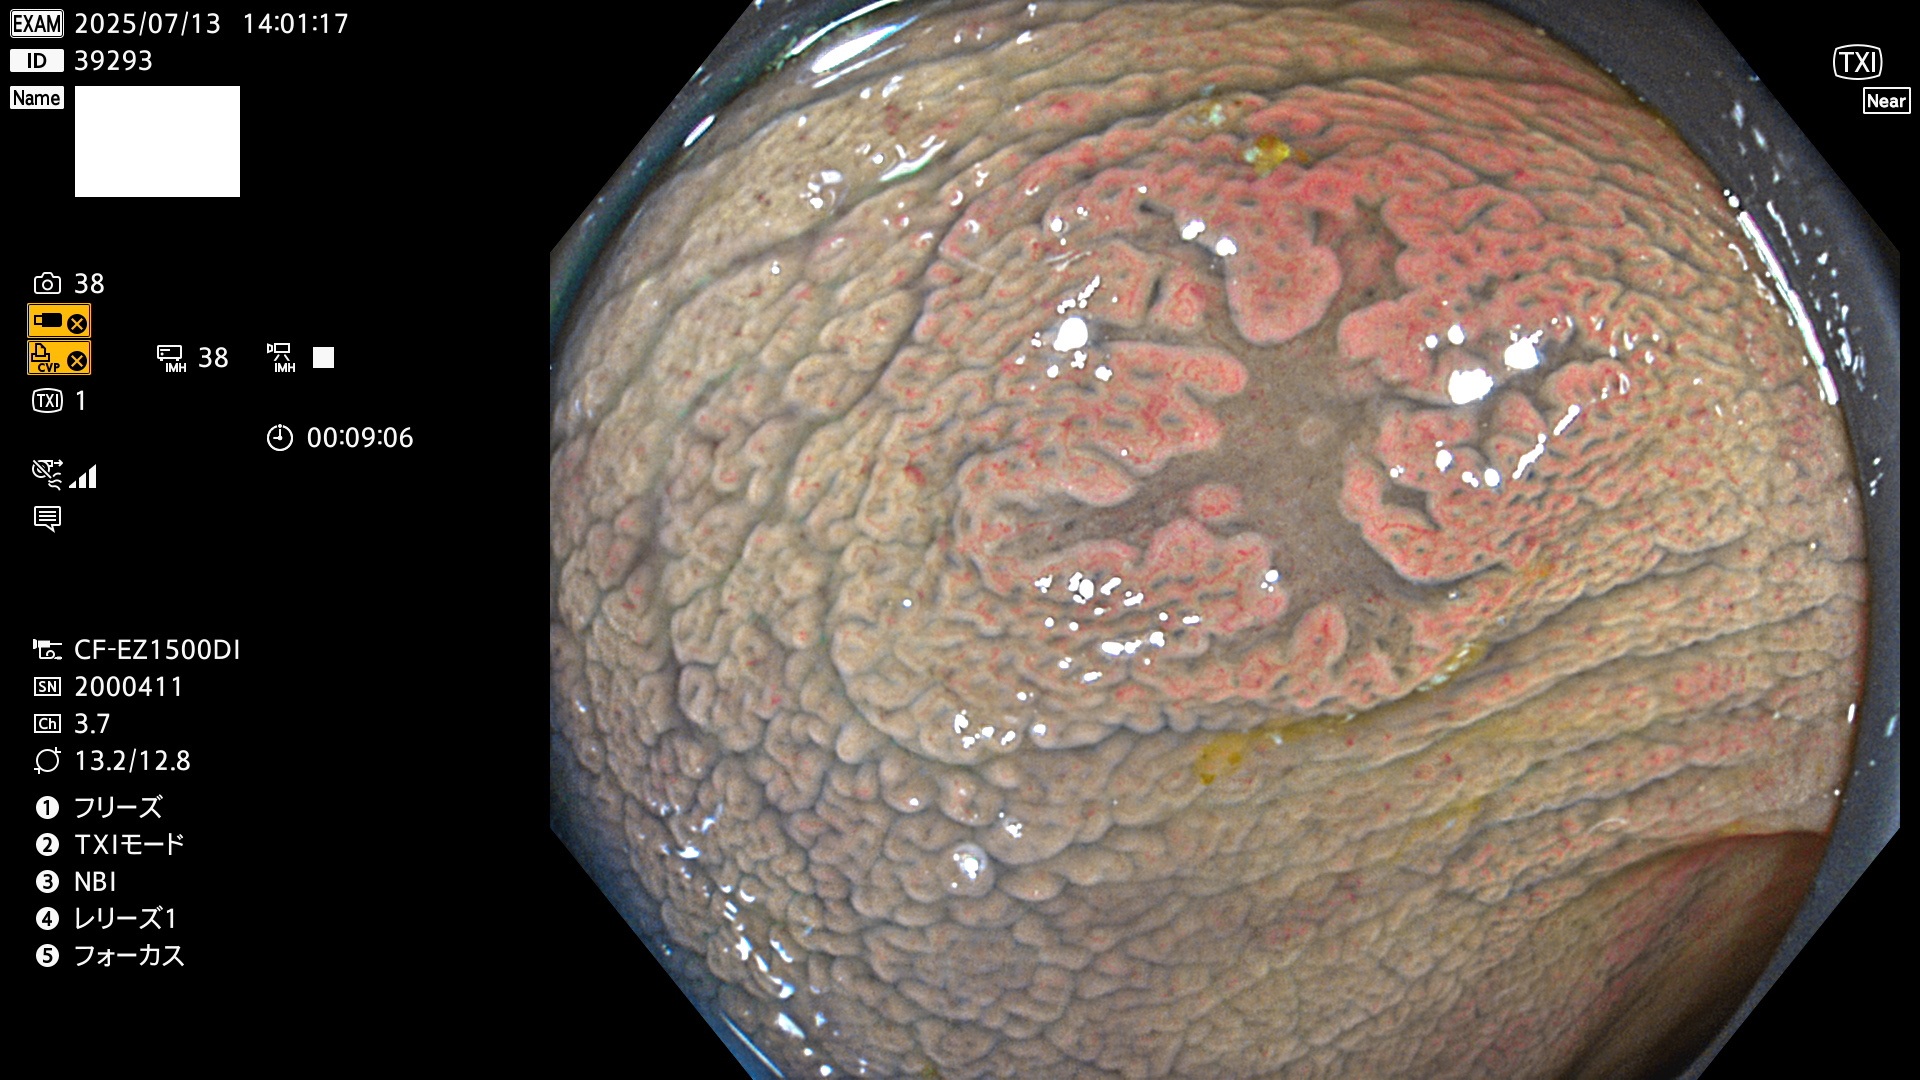

2025年7月10日〜7月13日の4日間(40件)15個 (Uc_ADR=15/40=38%)